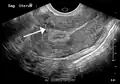

The presence of a uterine fibroid versus an adnexal tumor is made. Fibroids can be mistaken for ovarian neoplasms. An uncommon tumor which may be mistaken for a fibroid is Sarcoma botryoides. It is more common in children and adolescents. Like a fibroid, it can also protrude from the vagina and is distinguished from fibroids.[8] While palpation used in a pelvic examination can typically identify the presence of larger fibroids, gynecologic ultrasonography (ultrasound) has evolved as the standard tool to evaluate the uterus for fibroids. Sonography will depict the fibroids as focal masses with a heterogeneous texture, which usually cause shadowing of the ultrasound beam. The location can be determined and dimensions of the lesion measured. Also, magnetic resonance imaging (MRI) can be used to define the depiction of the size and location of the fibroids within the uterus.